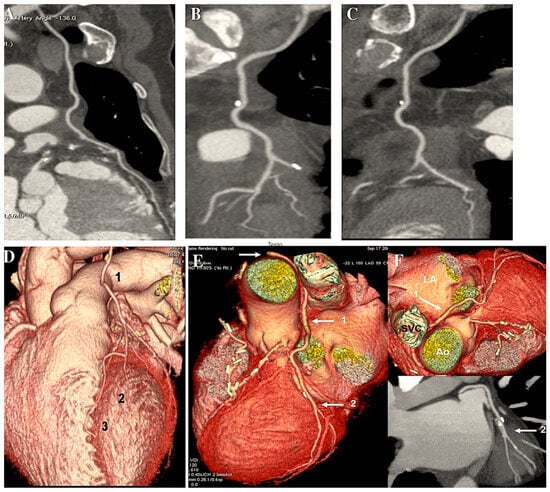

Two distinct meta-analyses have corroborated this conclusion over the past two years, not only in larger cohorts of patients but also with longer-term follow-up. A single study encompassed 27 observational reports comprising a total of 79,000 patients, comprising approximately one-quarter of those with BITA. The findings indicated a statistically significant reduction in long-term mortality rates with BITA (p < 0.00001) [189]. An investigation conducted by Yi and Associates [190] included nine observational series of over 15,000 patients, representing approximately half of whom had BITA, with follow-up lasting a mean period of nine years. The analysis revealed a notable decline in fatality rates associated with BITA (HR: 0.79; 95% CI: 0.75 to 0.84). It is noteworthy that no study has documented any adverse impact of BITA on the fatality rate (Figure 7).

CABG has been performed using best isolated technically appropriate anastomosis, either as an isolated termino-lateral graft with pediculate ITA or in a Y-shaped configuration with sequential BITA grafts. Controls have been achieved through the utilisation of computed tomography angiography. (A–F): The post-processing of computed tomography angiography of CABG was conducted using volume rendering and two-dimensional curved imaging with automatic tracking. (A–C): Illustrations of the utilisation of two-dimensional curved imaging in conjunction with automatic tracking in the context of CABG. (A): LITA has been anastomosed to the LAD. (B): LITA sequential grafting on LAD and the first diagonal branch. (C): RITA anastomosed on the first obtuse branch. (D–F): Volume rendering imaging of CABG. (D): 1. LITA, 2. LITA on the diagonal branch, and 3. LITA-LAD. (E,F): Illustrations of the grafting of the RITA on the CCA. The white arrow (1) indicates the course of the RITA between the aorta and the left atrium. (2) This image depicts distal grafting on the first obtuse branch. Abbreviations: CABG, coronary artery bypass grafting; CCA, circumflex coronary artery; LITA, left internal thoracic artery; LAA, left atrial appendance; LAD, left anterior descending artery; RCA, right coronary artery; RITA, right internal artery.